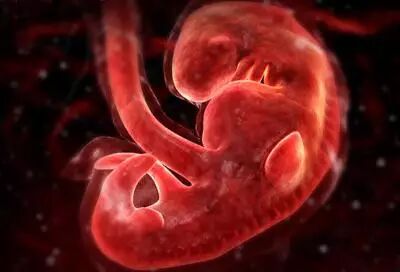

一个月:

标志着胚胎期的开始。身长约0.2厘米,体重约1克,。动脉、静脉已形成,且有血液流动;脑、肾、消化管已见雏形;脐带已开始工作;心脏形成且开始跳动。